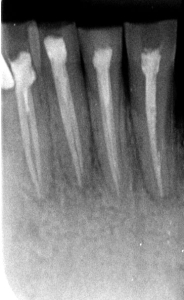

Unele afecțiuni ale dintelui, precum fisurile fine sau leziunile incipiente, nu pot fi detectate cu ochiul liber. Folosind microscopul le putem identifica din timp, chiar și la o mărire de 25 de ori, ceea ce permite tratamente corecte, eficiente și de durată.

În urma iritațiilor cronice de lungă durată, precum cariile vechi netratate, pulpa dentară poate suferi modificări profunde, retrăgându-se sau transformându-se prin calcifiere. Aceste situații fac tratamentul endodontic mult mai complex.

Realizarea cavității de acces în dinții cu camere pulpare calcifiate (pietre pulpare) reprezintă o provocare majoră și, în absența magnificației optice (vizualizare mărită), poate duce la pierderi semnificative de structură dentară sănătoasă. De aceea, utilizarea tehnologiei moderne de mărire de până la 25 de ori, este necesară pentru un tratament precis, sigur și minim invaziv.